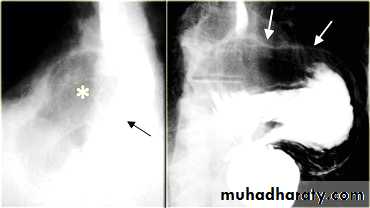

Esophageal Varieces

Dilatation of venous plexus in the wall of the esophagus due to increased pressure ( portal H.T.).Important cause of Hematemesis .

Early changes seen in the mucosa (D.C.) loss of parallelism with thick and tortuous folds.

Later multiple small filling defects (fine cobble stone).

In advanced stage large filling defects ( coarse cobble stone ) .

7More advanced stage elongated and worm like filling defect .

The changes are seen at lower third and gastric fundus.